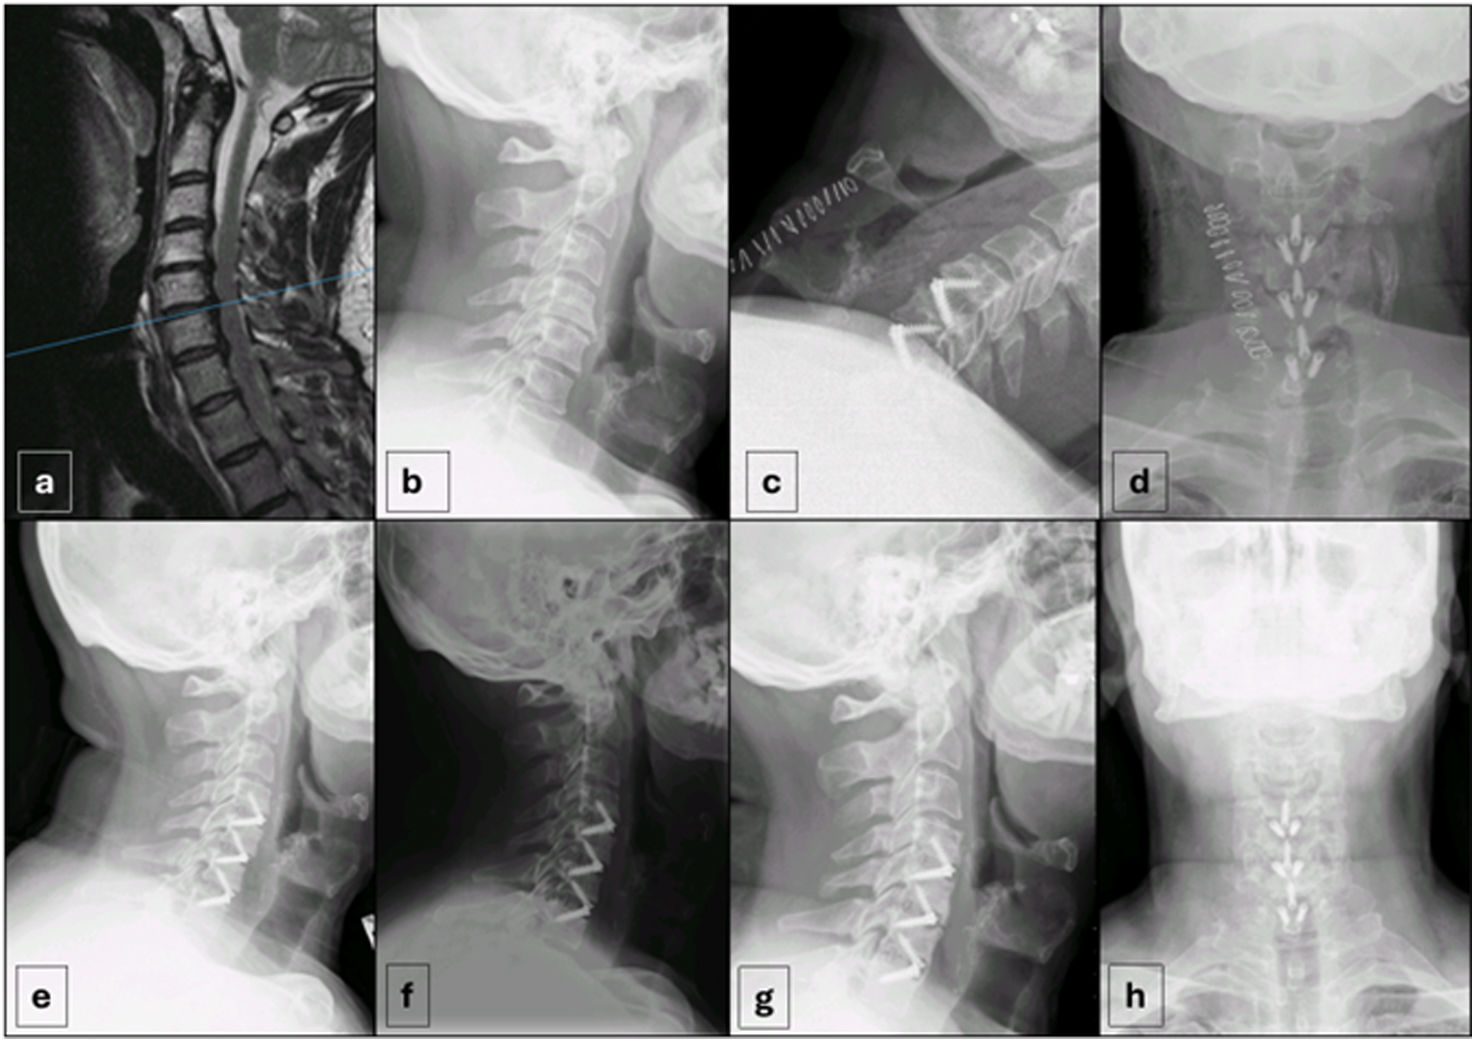

En la figura 5 se muestran radiografías representativas.

Radiografías representativas de la cohorte (caso 37). (a) RM sagital ponderada en T2 preoperatoria que demuestra estenosis cervical. (b) Radiografía lateral preoperatoria que muestra estrechamiento del espacio discal. (c y d) Radiografías postoperatorias inmediatas (vistas lateral y anteroposterior) tras la DFCA con una jaula de PEEK-titanio anclada. (e-h) Radiografías de seguimiento a largo plazo, incluidas vistas lateral, anteroposterior y de flexión/extensión dinámica, que demuestran el mantenimiento de la alineación, la fijación estable y la ausencia de movimiento segmentario.